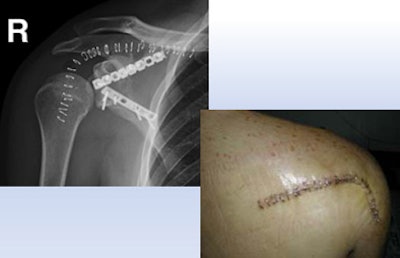

| A 23-year-old man presented with a dramatic fracture of the right scapula from an elevator accident (above). Use of a 3D model allowed surgeons to actually cut the scapula model and carefully design the plates to be implanted (below) before the patient was taken to surgery, leading to a shorter operation time and a successful outcome (bottom image). All images courtesy of Dr. Jacob Sosna. |